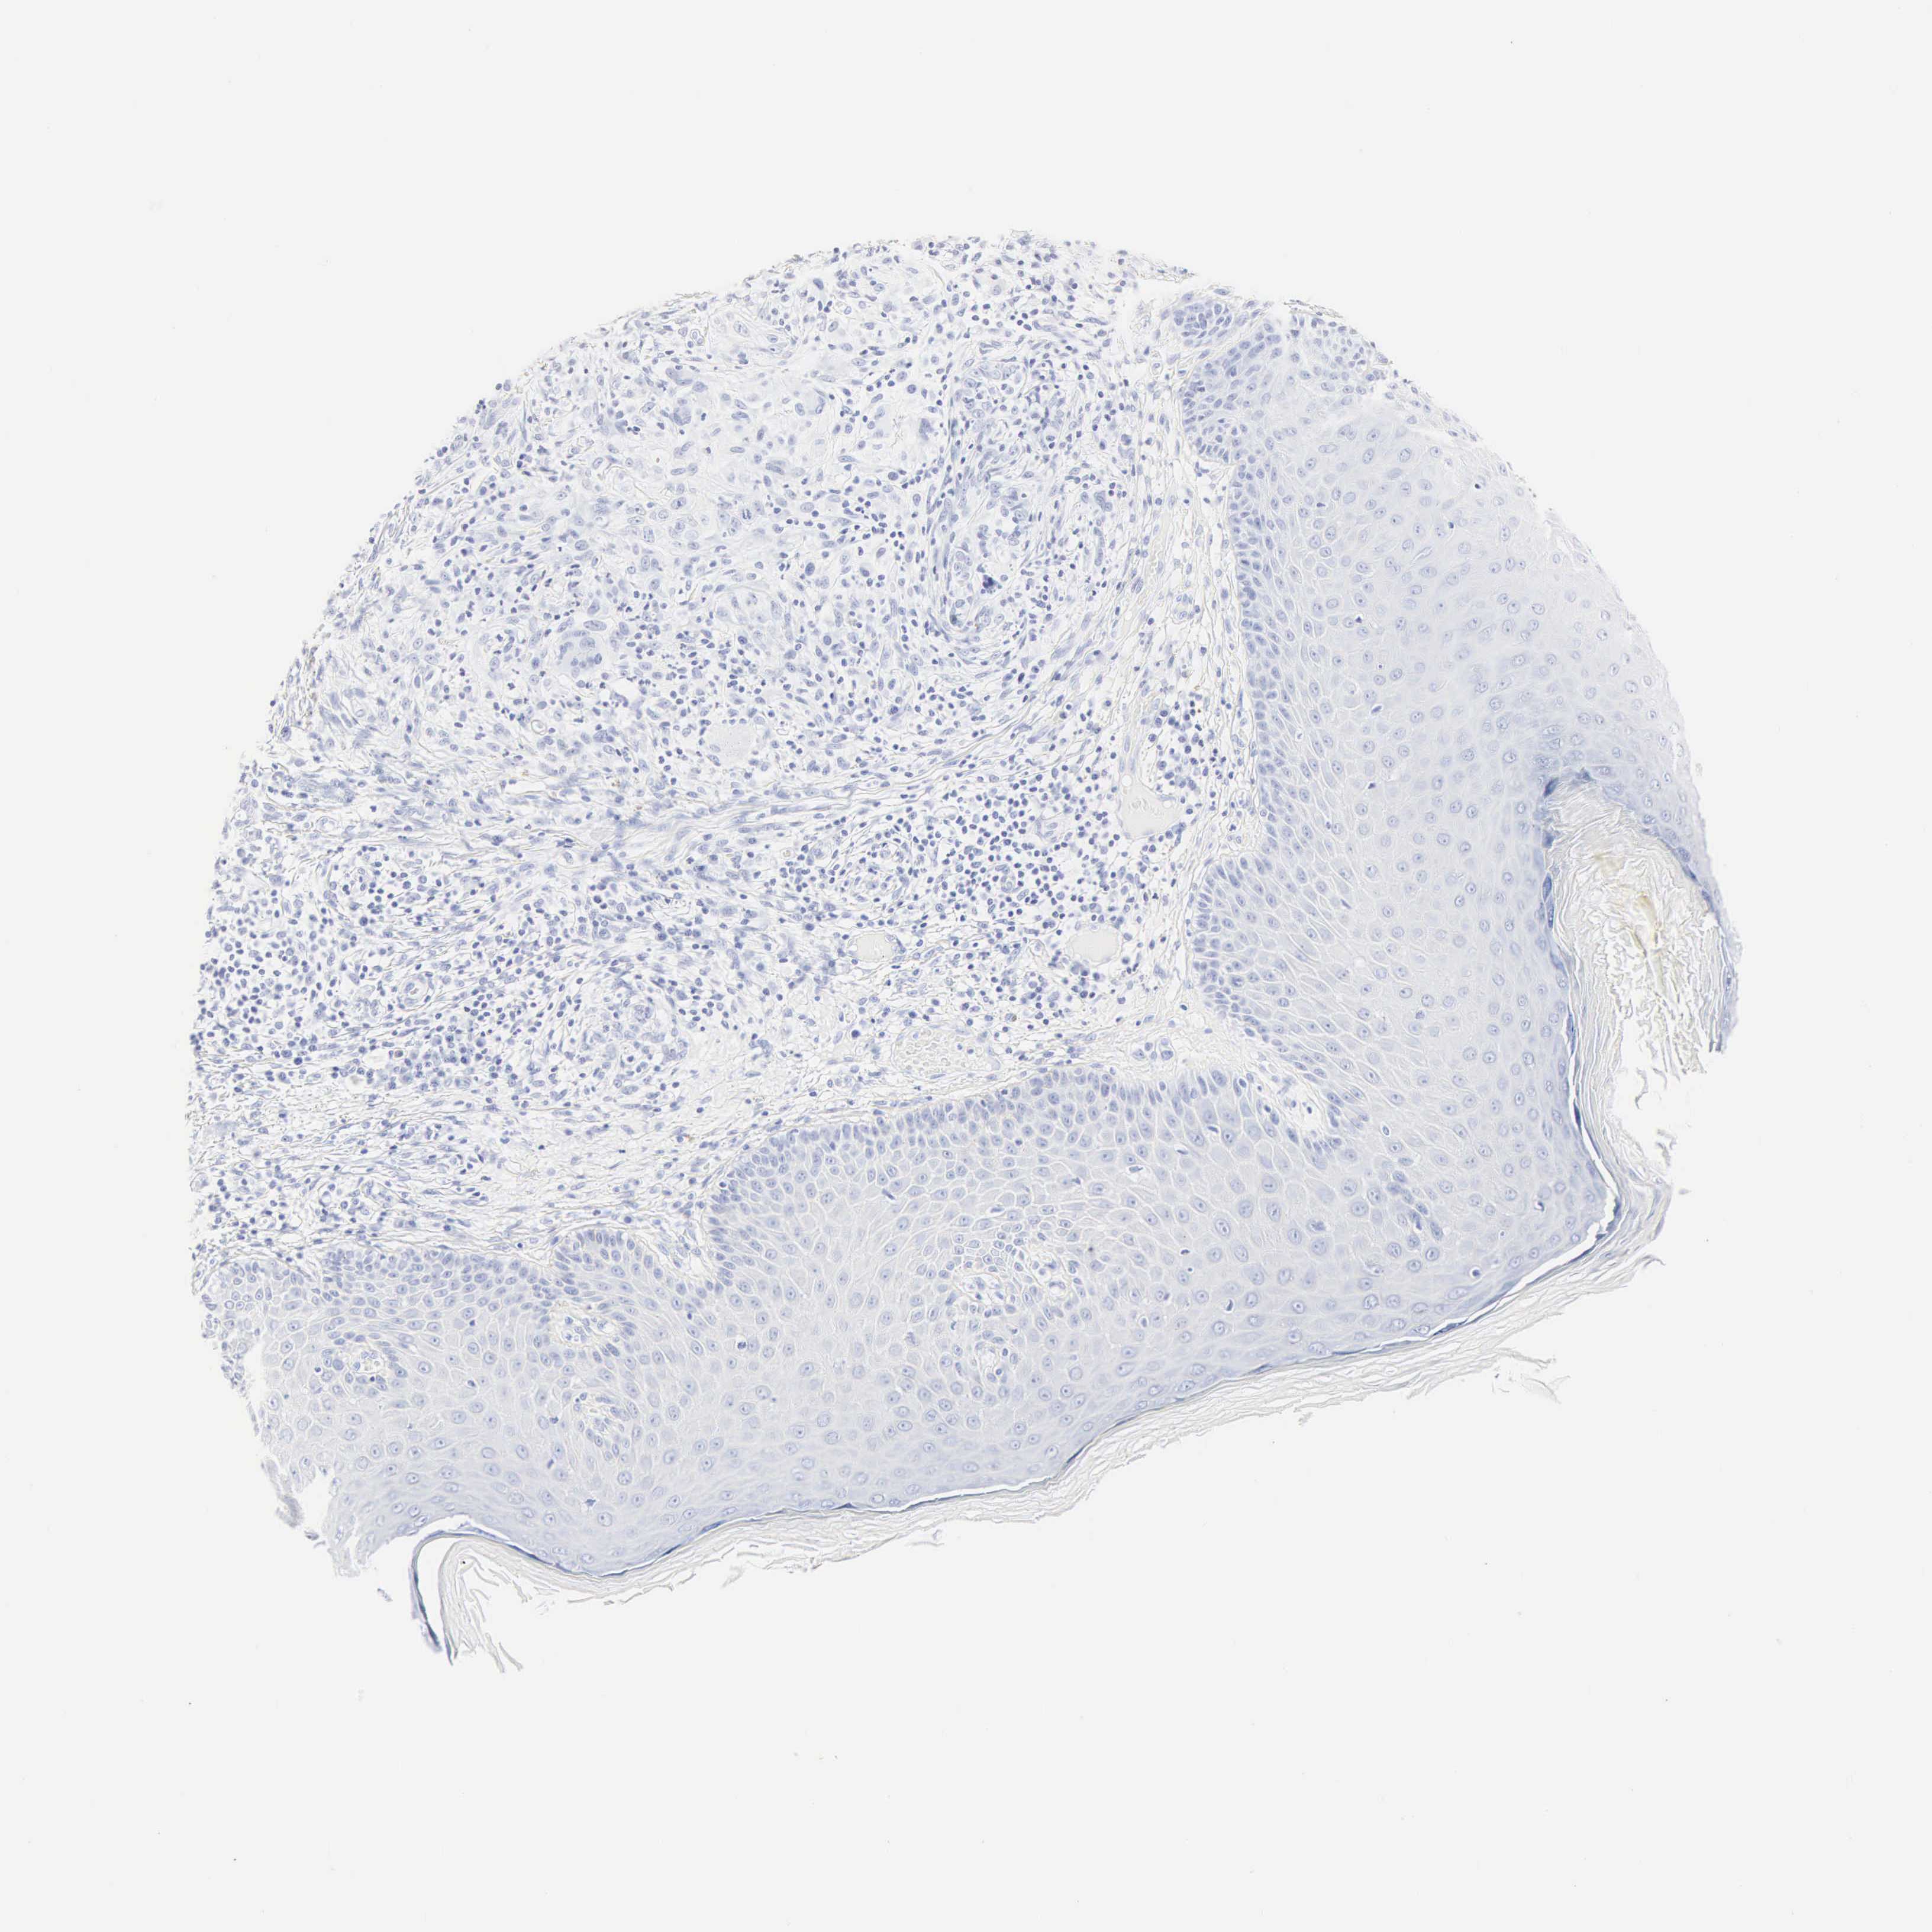

Basal cell and squamous cell cancer

SKIN CANCER - Protein expressioni

A mouse-over function shows sample information and annotation data. Click on an image to view it in a full screen mode. Samples can be filtered based on level of antibody staining by selecting one or several of the following categories: high, medium, low and not detected. The assay and annotation is described here.

Antibody stainingi

Antibody staining in the annotated cell types in the current human tissue is reported as not detected, low, medium, or high, based on conventional immunohistochemistry profiling in selected tissues. This score is based on the combination of the staining intensity and fraction of stained cells.

Each image is clickable and will lead to virtual microscopy that enables deeper exploration of all samples and also displays staining intensity scores, fraction scores and subcellular localization as well as patient and tissue information for each sample.

Antibody HPA038925

Antibody HPA038934

Antibody CAB000042

Antibody CAB010884

Basal cell carcinoma

Squamous cell carcinoma, NOS

Squamous cell carcinoma, metastatic, NOS